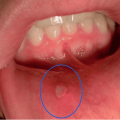

Ձվարանի քաղցկեղի 10 նախանշաններ, որոնք երբեք չի կարելի անտեսել